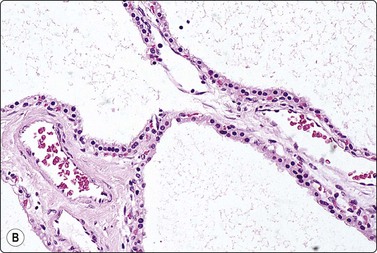

Serous cystadenoma (microcystic/glycogen-rich adenoma) (Fig. 11.6)

These are uncommon benign lesions, often incidental findings in older individuals. Their presentation must be familiar to cytopathologists, as failure to identify the constituent bland monolayered sheets might result in an erroneous ‘nonrepresentative’ report. Histopathologically, these tumors demonstrate classic microcysts, lined by bland, uniform glycogen-rich mucin-negative cells (Fig. 11.6).59 Several reports have appeared in the literature on FNB cytodiagnosis.58,60,61 The aspirate is clear and watery, some are acellular, while others contain a sparse exfoliate of monomorphic round cells with finely vacuolated, glycogen-positive, mucin-negative cytoplasm, and centrally disposed nuclei containing fine chromatin. Occasionally, larger monolayered sheets may be obtained (Fig. 11.6). The cell groups may resemble mesothelial cells or bland acinar cells. Cell features are thus non-specific, but are assessed in conjunction with the watery nature of the aspirate and the very characteristic radiological picture of small microcysts within a well-demarcated round mass lesion arising anywhere in the pancreas. A PAS stain will highlight the glycogen-rich cytoplasm.

image image

Fig. 11.6 Serous cystadenoma

(A) Watery aspirate with a few monolayered sheets of epithelial cells with small round uniform nuclei and moderate pale cytoplasm; see inset (Pap, HP); (B) Corresponding tissue section (H&E, IP).

Biochemical analysis of cyst fluid generally shows a low viscosity and low CEA and amylase levels.62 A recent study which combined imaging, biochemical and cytological data in reaching a diagnosis concluded that the preoperative diagnosis of serous cystadenomas remains a challenge.63